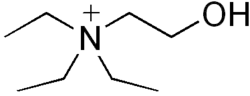

Triethylcholine

| Formula | C8H20NO |

| Molar mass | 146.254 g·mol−1 |

Triethylcholine is a drug which mimics choline, and causes failure of cholinergic transmission by interfering with synthesis of acetylcholine in nerve endings.[1]